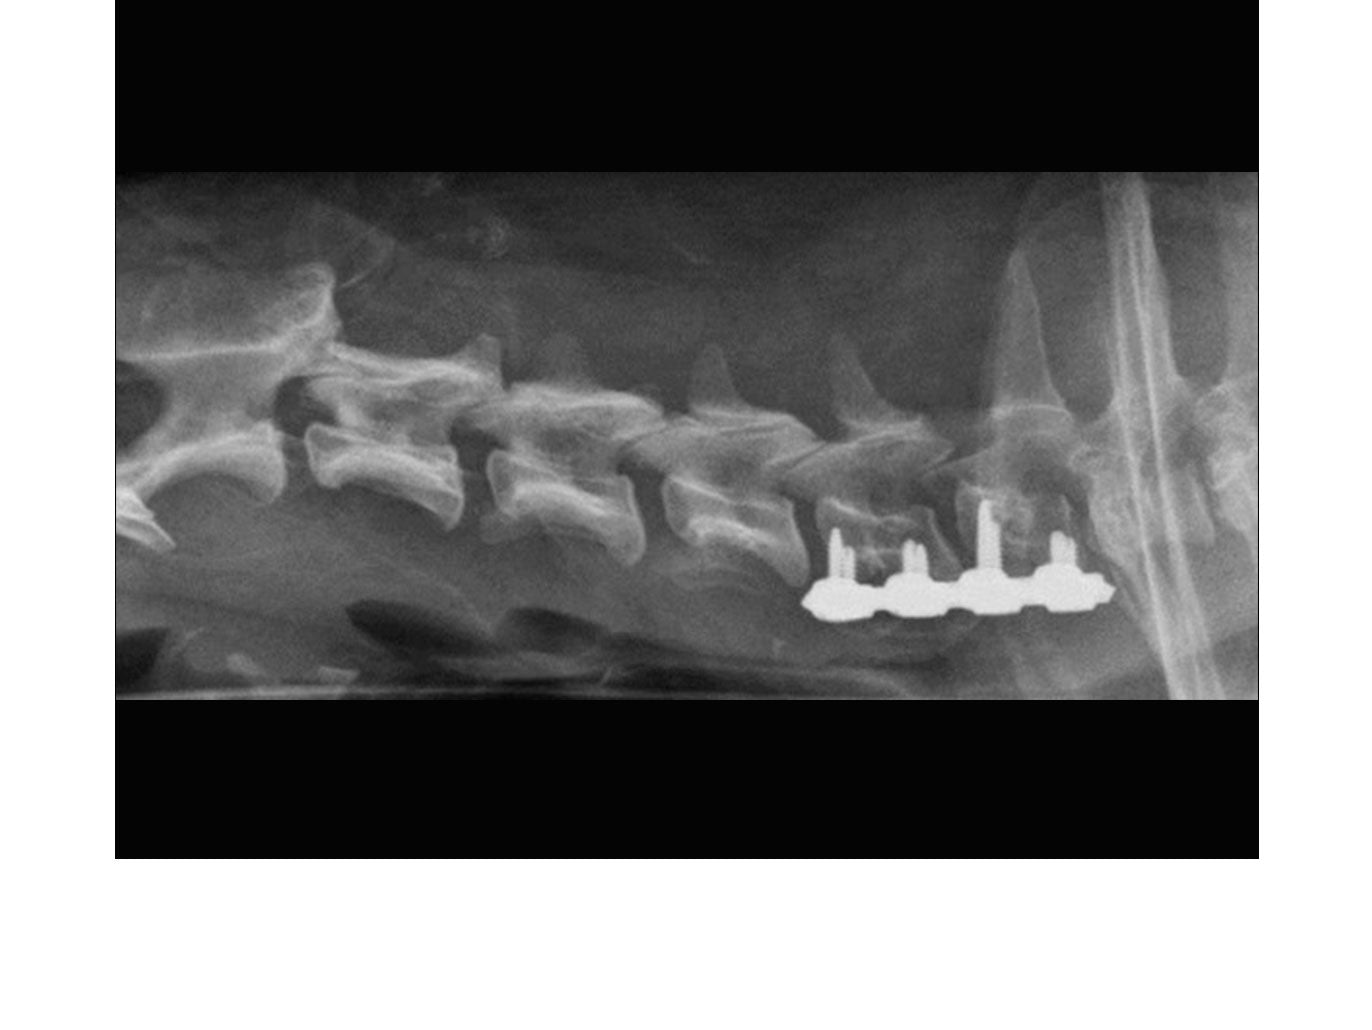

• Cervical - ventral aspects of vertebrae

SOP™ uniquely offers a spinal stabilization system with reasonable cost. The SOP™ plates are commonly used in pairs with the screws engaging vertebral pedicles or bodies. The SOP™ can be used similarly to a pedicle screw system for the thoracolumbar spine, or as a locking anterior system for cervical stabilisation/fusions.

// User Cases

Highlighting the cases of these products in real-life situations is vital to demonstrating their success. Below are cases studies of long-term follow up surgeries.